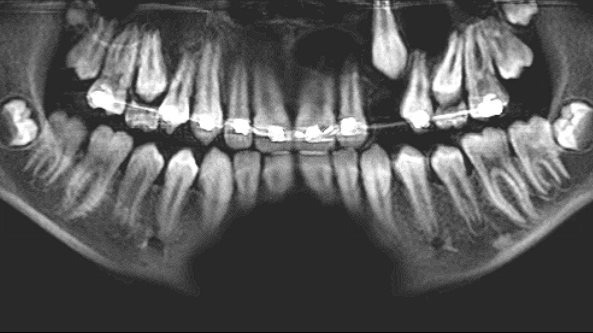

A 13-year-old male was noted by his orthodontist to have an expanding radiolucency encompassing impacted tooth no. 11. The patient was without complaint, and his medical history was otherwise unremarkable. A CT scan revealed a multilocular radiolucency extending from the maxillary midline to the area of the left permanent second molar and expanding into the left maxillary sinus. Cortical expansion in the area of the lesion was notable and all adjacent teeth were vital.

Treatment for case no. 2

The keratocystic odontogenic tumor of the left maxilla presented a much more complicated scenario for this patient as complete removal via enucleation and curettage would require removal of permanent teeth nos. 9–15, and most of the associated alveolus. The floor of the maxillary sinus was obliterated by the cyst as well, so complete removal in this fashion would have resulted in a near hemimaxillectomy, producing a catastrophic defect for this patient. This defect would not have been just physically difficult to endure, but given the patient’s age, psychologically devastating as well.

These factors prompted a decision to treat this lesion with marsupialization, with a plan to later enucleate any residual lesion. Marsupialization involves opening the cavity of the cyst and suturing the lining to the oral mucosa, creating a permanent opening from the cyst cavity into the oral cavity. Once this is complete, the cyst will typically slowly decrease in size via appositional bone formation at the periphery of the cavity. Once the cavity has sufficiently decreased in size, the remaining lesion can be removed via enucleation and curettage as described in the first case.

At the time of publication, the lesion described had reduced in size dramatically, now extending from tooth nos. 10–12. The floor of the maxillary sinus ossified as well. The time elapsed since the marsupialization procedure was six months. Removal of the residual cyst with immediate bone grafting would be performed shortly, likely including the sacrifice of the lateral incisor and second bicuspid. Although this is a large defect, it will be much more easily managed than that posed if marsupialization had not been utilized (figure 7).